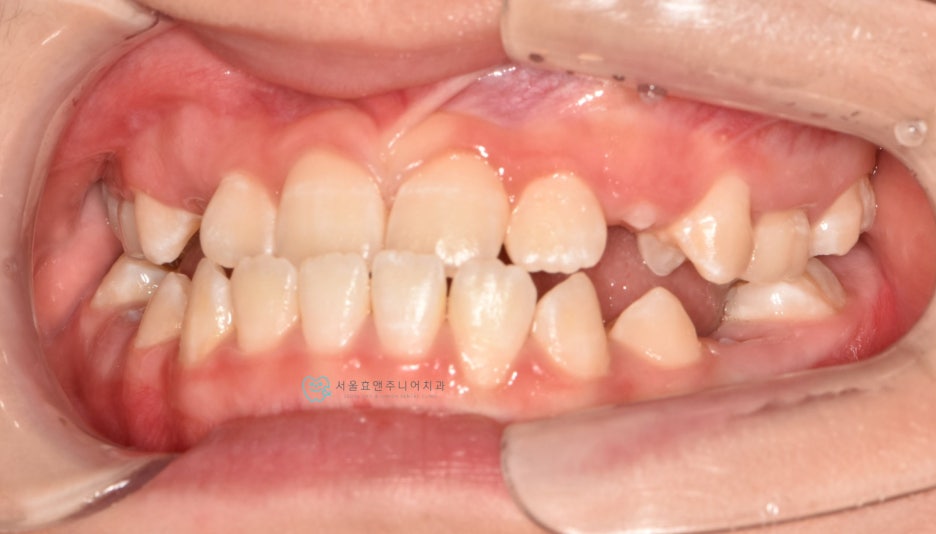

다음 케이스입니다.

너무 예쁜 10세 11개월의 여자친구인데 반대교합이 있네요.

초진사진입니다. 앞니의 반대교합이 보입니다.